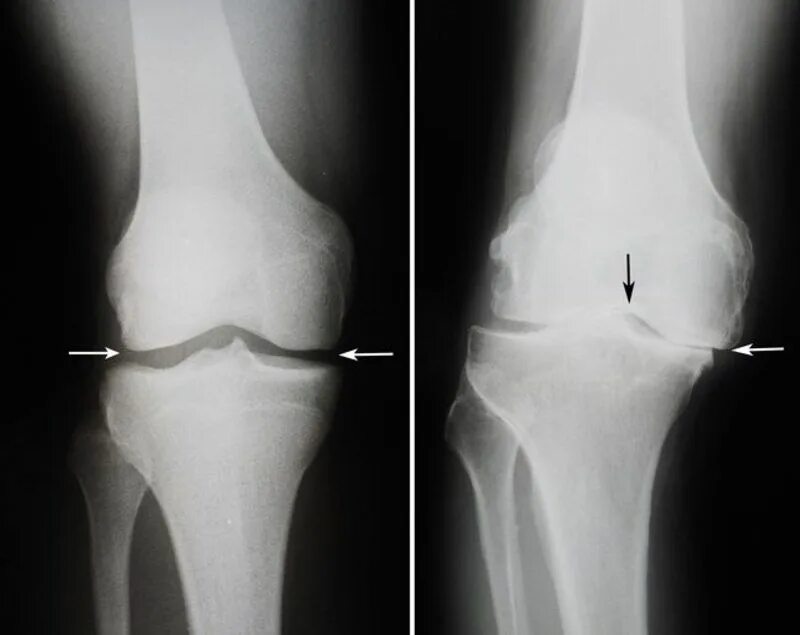

Деформирующий артроз коленных